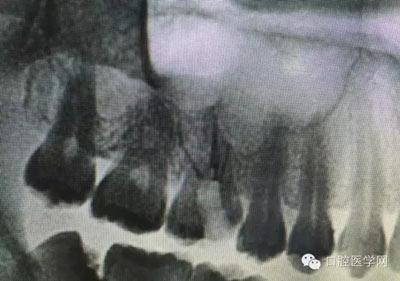

根管再治療是我們比較頭疼的,尤其是那些冠修復過的,我們有很多的麻煩需要去溝通,比如可能導致的側穿、可能沒有看到的腐質、可能導致的崩瓷,或者是后期可能出現(xiàn)冠折......這些需要我們和患者好好的溝通。全瓷冠還好些,金屬冠根測的時候很是麻煩,總之我們做修復的時候不要單純的追求速度,追求效益,適當?shù)淖⒁庀挛覀兊幕A治療和設計。

根管治療,我們在大學的時候就學習的東西,標準就在那里放著,可是很多時候我們熟視無睹,放任我們的想象去做。我們多些重視,多些心思,會好很多,認真對待每顆牙齒。